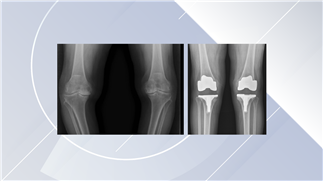

인공관절 수술은 언제, 어떻게 하는 수술인가요?

심한 무릎 퇴행성 관절염이 있는 환자에서 여러 가지 치료를 했음에도 효과가 없는 경우 마지막으로 선택할 수 있는 방법이 인공관절 수술입니다. 비교적 55세 이상의 고령에서 고려해볼 수 있습니다. 특별한 문제없이 잘 진행된 경우라면 수술 후 2-3일부터 보행이 가능하고 1주 이후부터는 일상생활이 가능합니다.